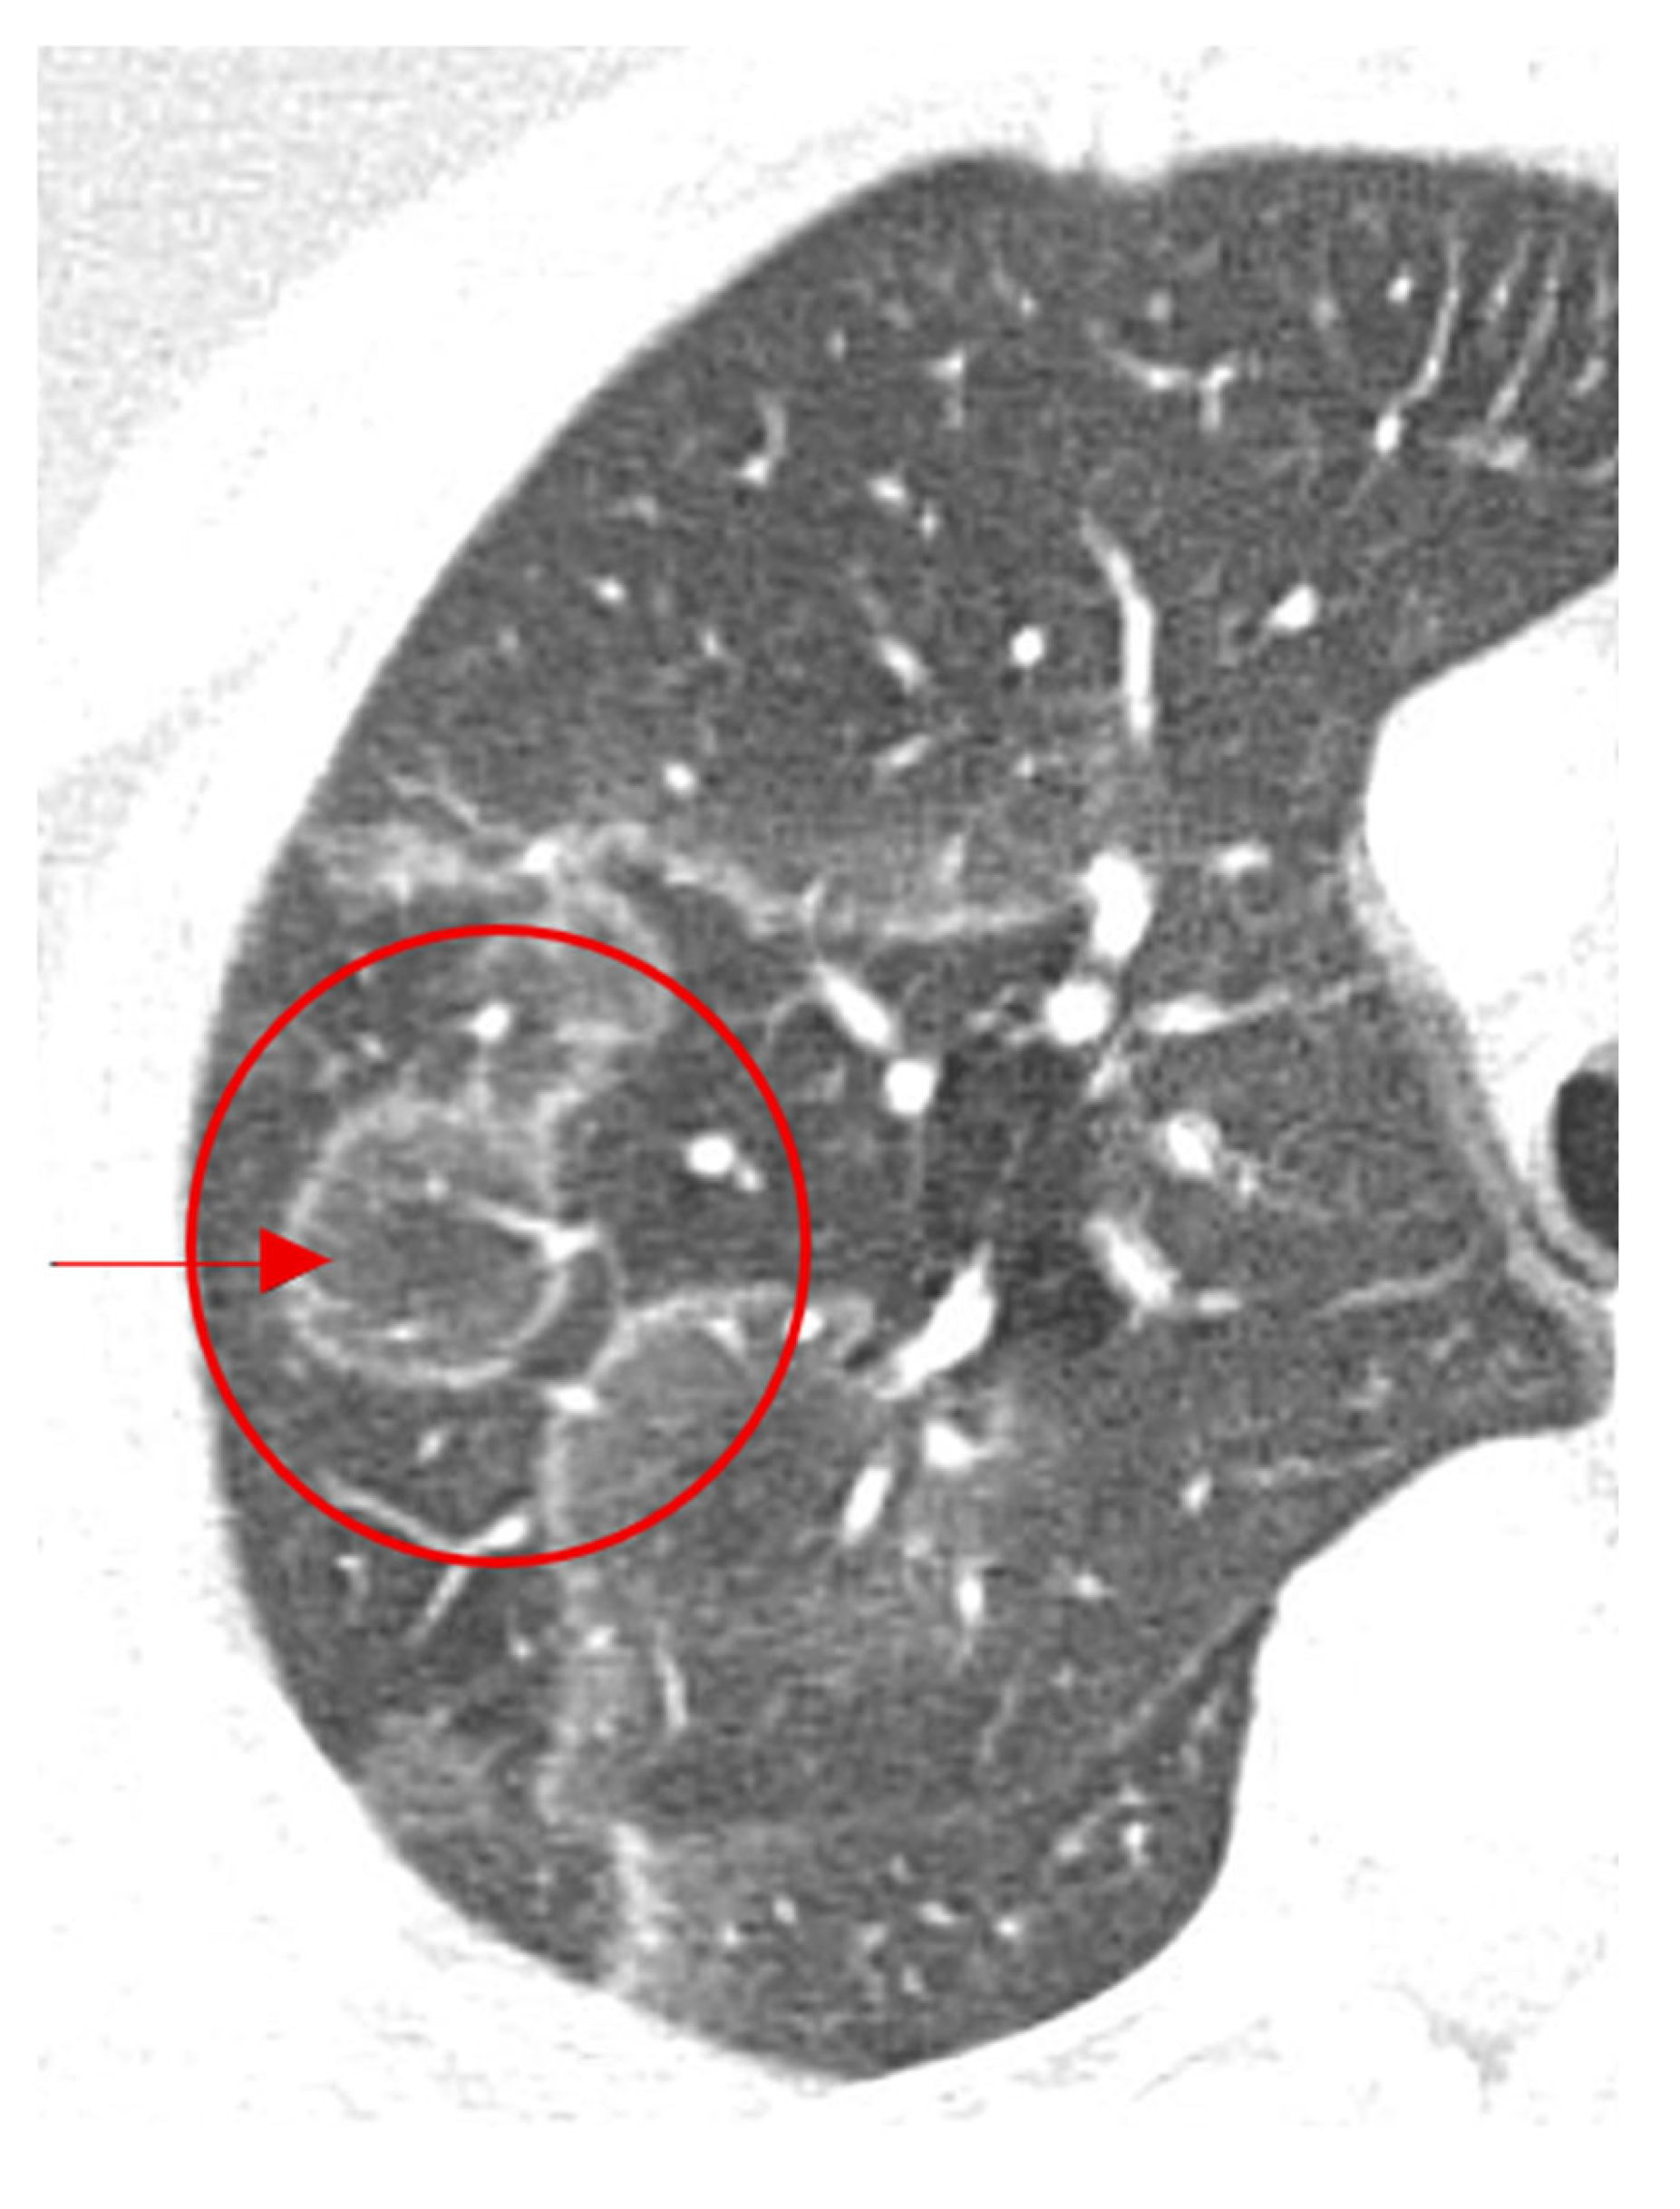

2.15. Halo Sign

2.15.2. On CT

- Pinto, P. The CT Halo Sign. Radiology 2004, 230, 109–110. [Google Scholar] [CrossRef] [PubMed]

- Georgiadou, S.P.; Sipsas, N.V.; Marom, E.M.; Kontoyiannis, D.P. The diagnostic value of halo and reversed halo signs for invasive mold infections in compromised hosts. Clin. Infect. Dis. 2011, 52, 1144–1155. [Google Scholar] [CrossRef] [PubMed]